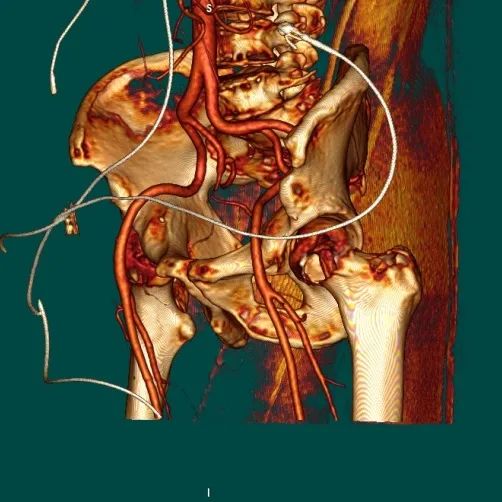

3D入路全程

R/L股动脉分叉位置

主入路条件

左冠风险评估